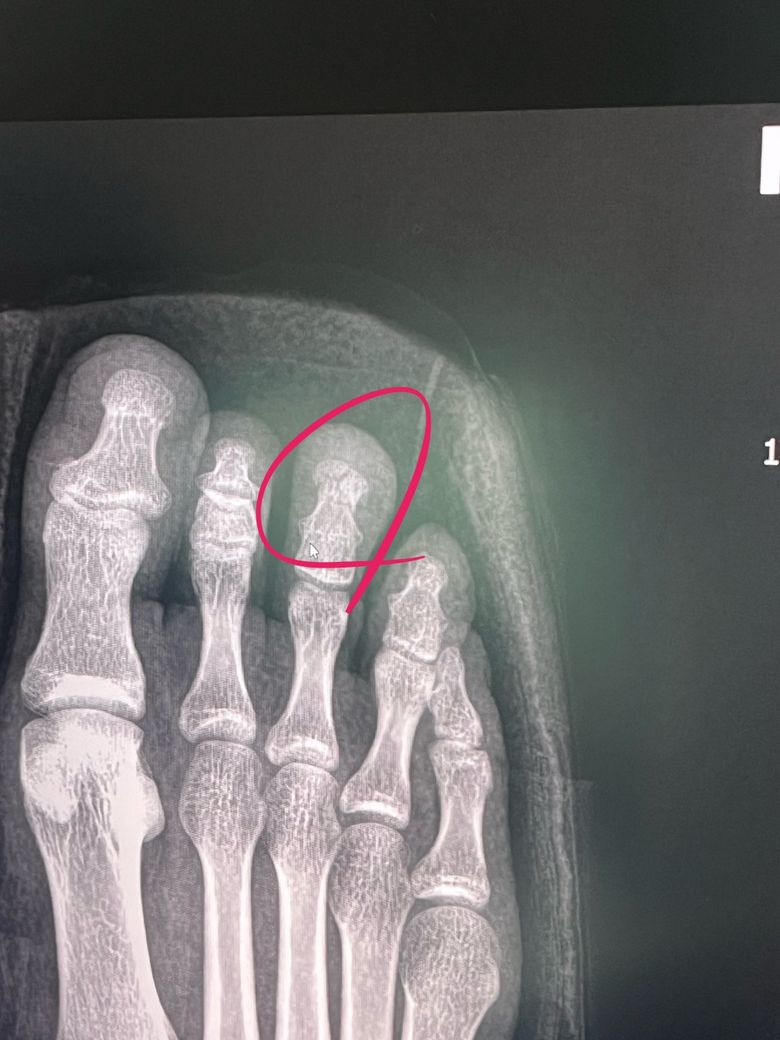

오른발 가운데 발가락에 무거운게 떨어져서 발톱이 떨어지고 발톱아래 뼈가 부서졌어요. 집앞 의사선생님이 수술은 꼭 안해도 된다고 하셨는데 어떻게 생각하시나요?

첫 번째 사진이 가운데 발가락 뼈가 부서진 상태이고요. 두 번째 사진은 발가락 뼈를 물리적으로 붙여논 상태입니다. 수술이 어려울거라고 하셔서 수술을 하지 않은 상태이며, 사고가 발생한지 3일차 입니다.

• 1번 째 사진

• 발가락 끝부분이고 뼈가 많이 전위되지 않아서 굳이 수술이 필요한 병변으로 보이지 않습니다

먼저 진료를 받으신 선생님 말씀을 따르시면 될 것 같습니다.

발가락 뼈가 부서졌어도 안정적으로 고정되어 있고 감염 혈액순환 문제 없고 비수술 치료도 가능합니다. 골절 부위가 잘 맞춰져 있고 움직임이 제한된다면 깁스나 부목 고정과 함께 충분한 휴식이 중요합니다 다만 부종 통증이 심하거나 뼈 배열이 불안정하면 수술이 필요할 수 있으니 정기 검진이 필수입니다!